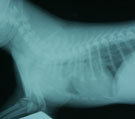

強い乾性発咳。一日中、続いた。 胸部レントゲンにて確認できる気道内異物なし 気管支鏡所見。気管内に発赤みられたが異物なし。 5日後。咳は全くなくなった。

経過:受診時、全身状態は良好であったが強い乾性発咳が続いていた。ぬいぐるみやペットボトルのふたやプラスチックのスプーンをボロボロになるまでかじる癖があるとのことだった。気道内異物が疑われたがレントゲンでは異物は見出せなかった。そこで異物か気管虚脱の鑑別のため気管支鏡検査を行った。体格が非常に小さいので気管分岐部までの観察とした。気管から左右主気管支に異物はなく気管虚脱もみられなかった。気管の膜性壁の一部に強い発赤がみられ物理的な損傷があったことが推測された。急性気管炎と診断された。治療はステロイドのみとした。検査後5日で咳はほとんど消失し、その2日後退院となった。